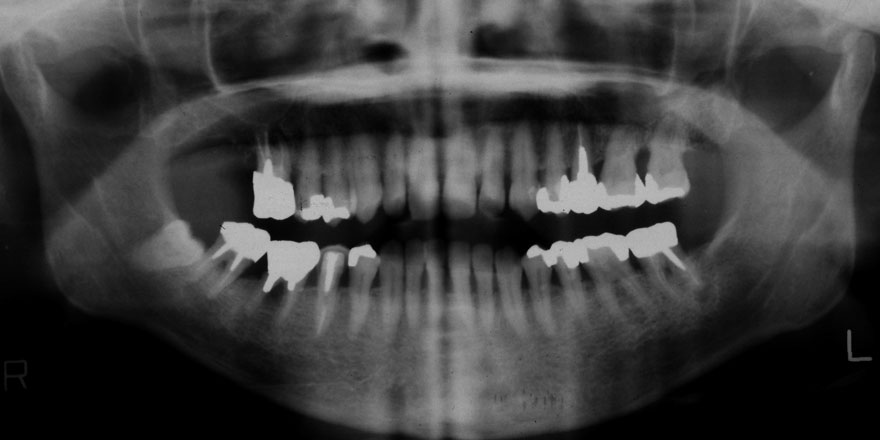

初診時 24歳 女性 平均歯槽骨喪失量:1.57mm

河田歯科医院

22年後 46歳

平均歯槽骨喪失量:1.72mm

22年間喪失量:-0.15mm

年間喪失速度:-0.007mm

(ケア頻度:1.35ヵ月ごと)